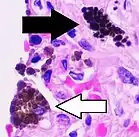

![]() Cytology of a macrophage with typical features. Wright stain. | |